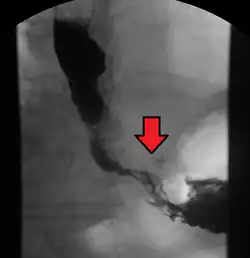

Although an occlusive tumor may be suspected on a barium swallow or barium meal, the diagnosis is best made with an examination using an endoscope. This involves the passing of a flexible tube with a light and camera down the esophagus and examining the wall, and is called an esophagogastroduodenoscopy. Biopsies taken of suspicious lesions are then examined histologically for signs of malignancy.

-

Endoscopic image of Barrett esophagus – a frequent precursor of esophageal adenocarcinoma -

Endoscopy and radial endoscopic ultrasound images of a submucosal tumor in the central portion of the esophagus -

Contrast CT scan showing an esophageal tumor (axial view)

Contrast CT scan showing an esophageal tumor (coronal view)